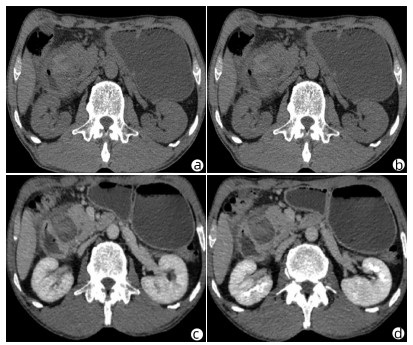

Heterotopic pancreas of the duodenum misdiagnosed as intraperitoneal tumor: A report of three cases

2022, 38(3): 643-645. DOI: 10.3969/j.issn.1001-5256.2022.03.030

Abstract(760) HTML (351) PDF (3871KB)(58)

Abstract: